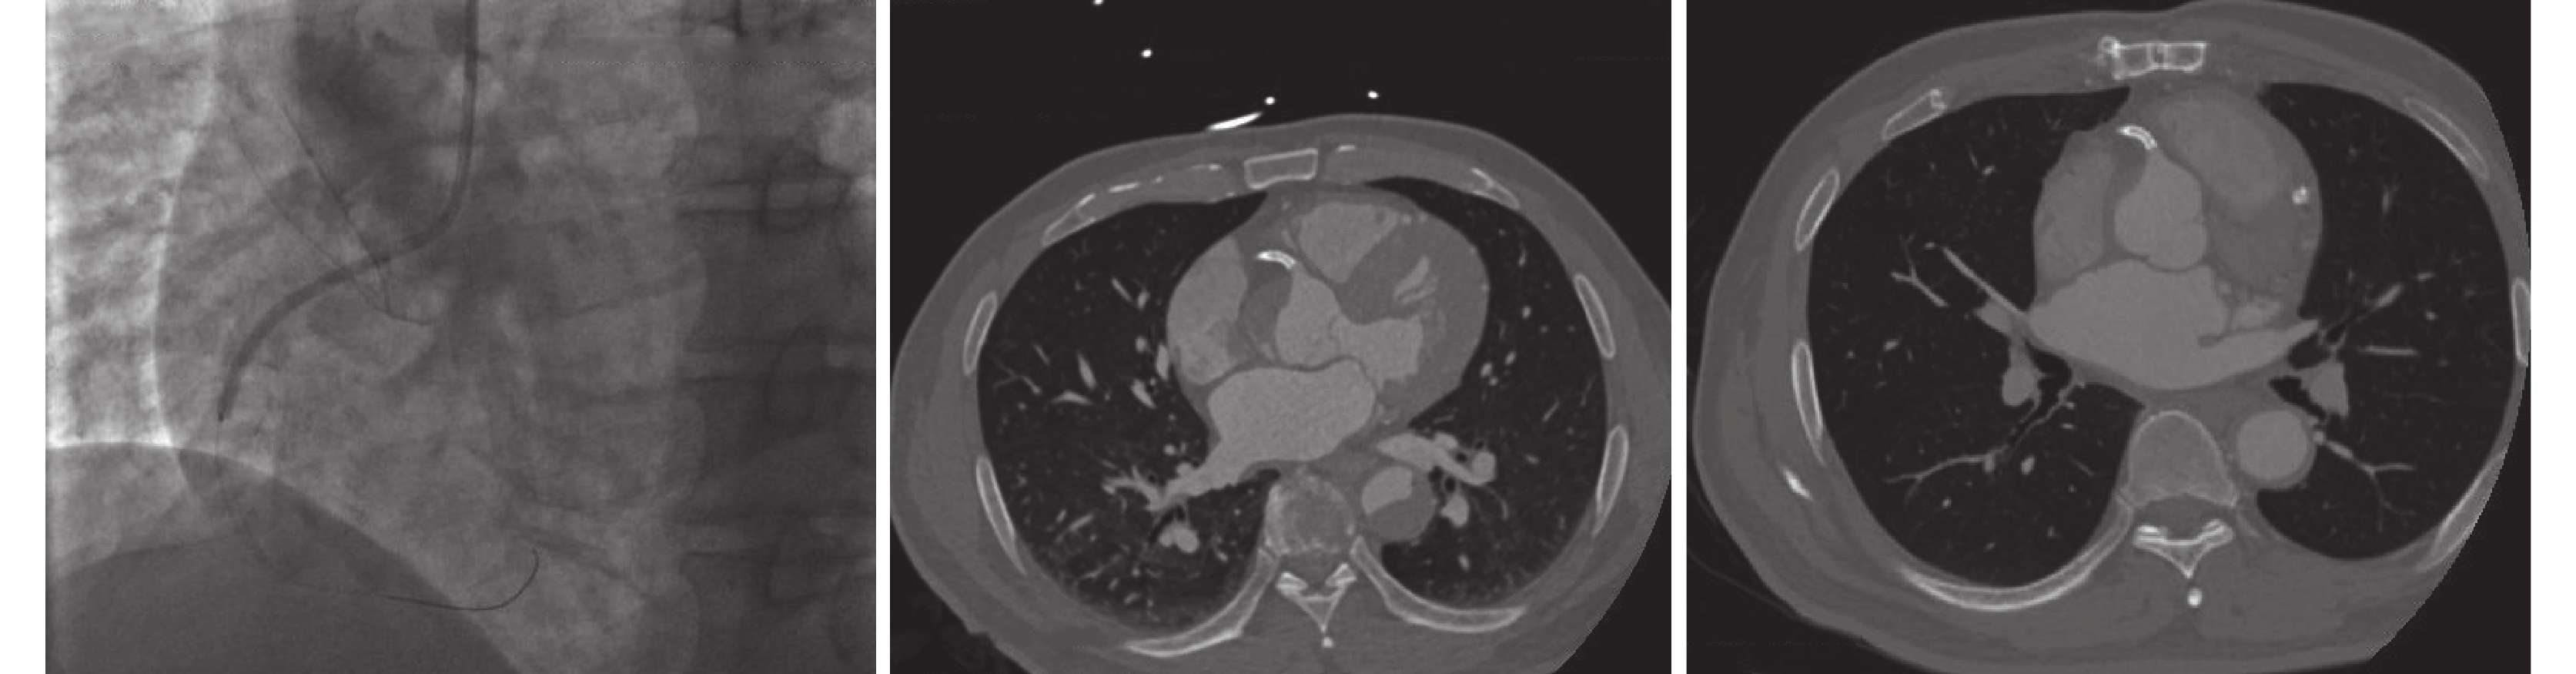

合并冠脈支架植入的Stanford A型主動脈夾層手術中冠脈的處理仍然是一大難題,根據我們的經驗,前面提到的三類患者中第三類冠心病患者既往PCI病史的多數術前沒有相關的冠脈檢查,手術中需要通過心臟復跳的情況來判斷是否需要搭橋。第一和第二類患者因為術前冠脈造影檢查能夠準確了解冠脈病變情況,對術中冠脈處理有積極的指導意義。根據我們的經驗,第一類患者是術中同期行旁路移植術最多的,這與患者本身合并冠脈病變有關,同時往往因夾層累及導致冠脈病變更加嚴重。而第二類患者往往不合并冠心病,多為主動脈夾層累及冠脈開口所致,文獻[13-14]報道Stanford A型主動脈夾層累及冠脈的發生率約為6%~19%,Neri等[15]將其分為三型:A型:局限于冠脈開口的內膜剝離;B型:內膜剝離至冠脈內,冠脈假腔形成(假腔多位于冠脈上方);C型:冠脈內膜套筒樣剝離并離斷。B型與C型更容易被誤診為ACS而行PCI,雖然支架在一定程度上可能緩解了心肌灌注不良的情況,但是給手術造成了一定的難度,本組有4例患者術中取出了位于右冠開口的支架;見圖2。我們的經驗是可根據支架釋放的位置和時間長短選擇是否取出支架,結合主動脈根部受累的情況選擇升主動脈置換或者Bentall手術;見圖3。無法重建冠脈開口的則選擇縫閉冠脈開口后行旁路移植術。